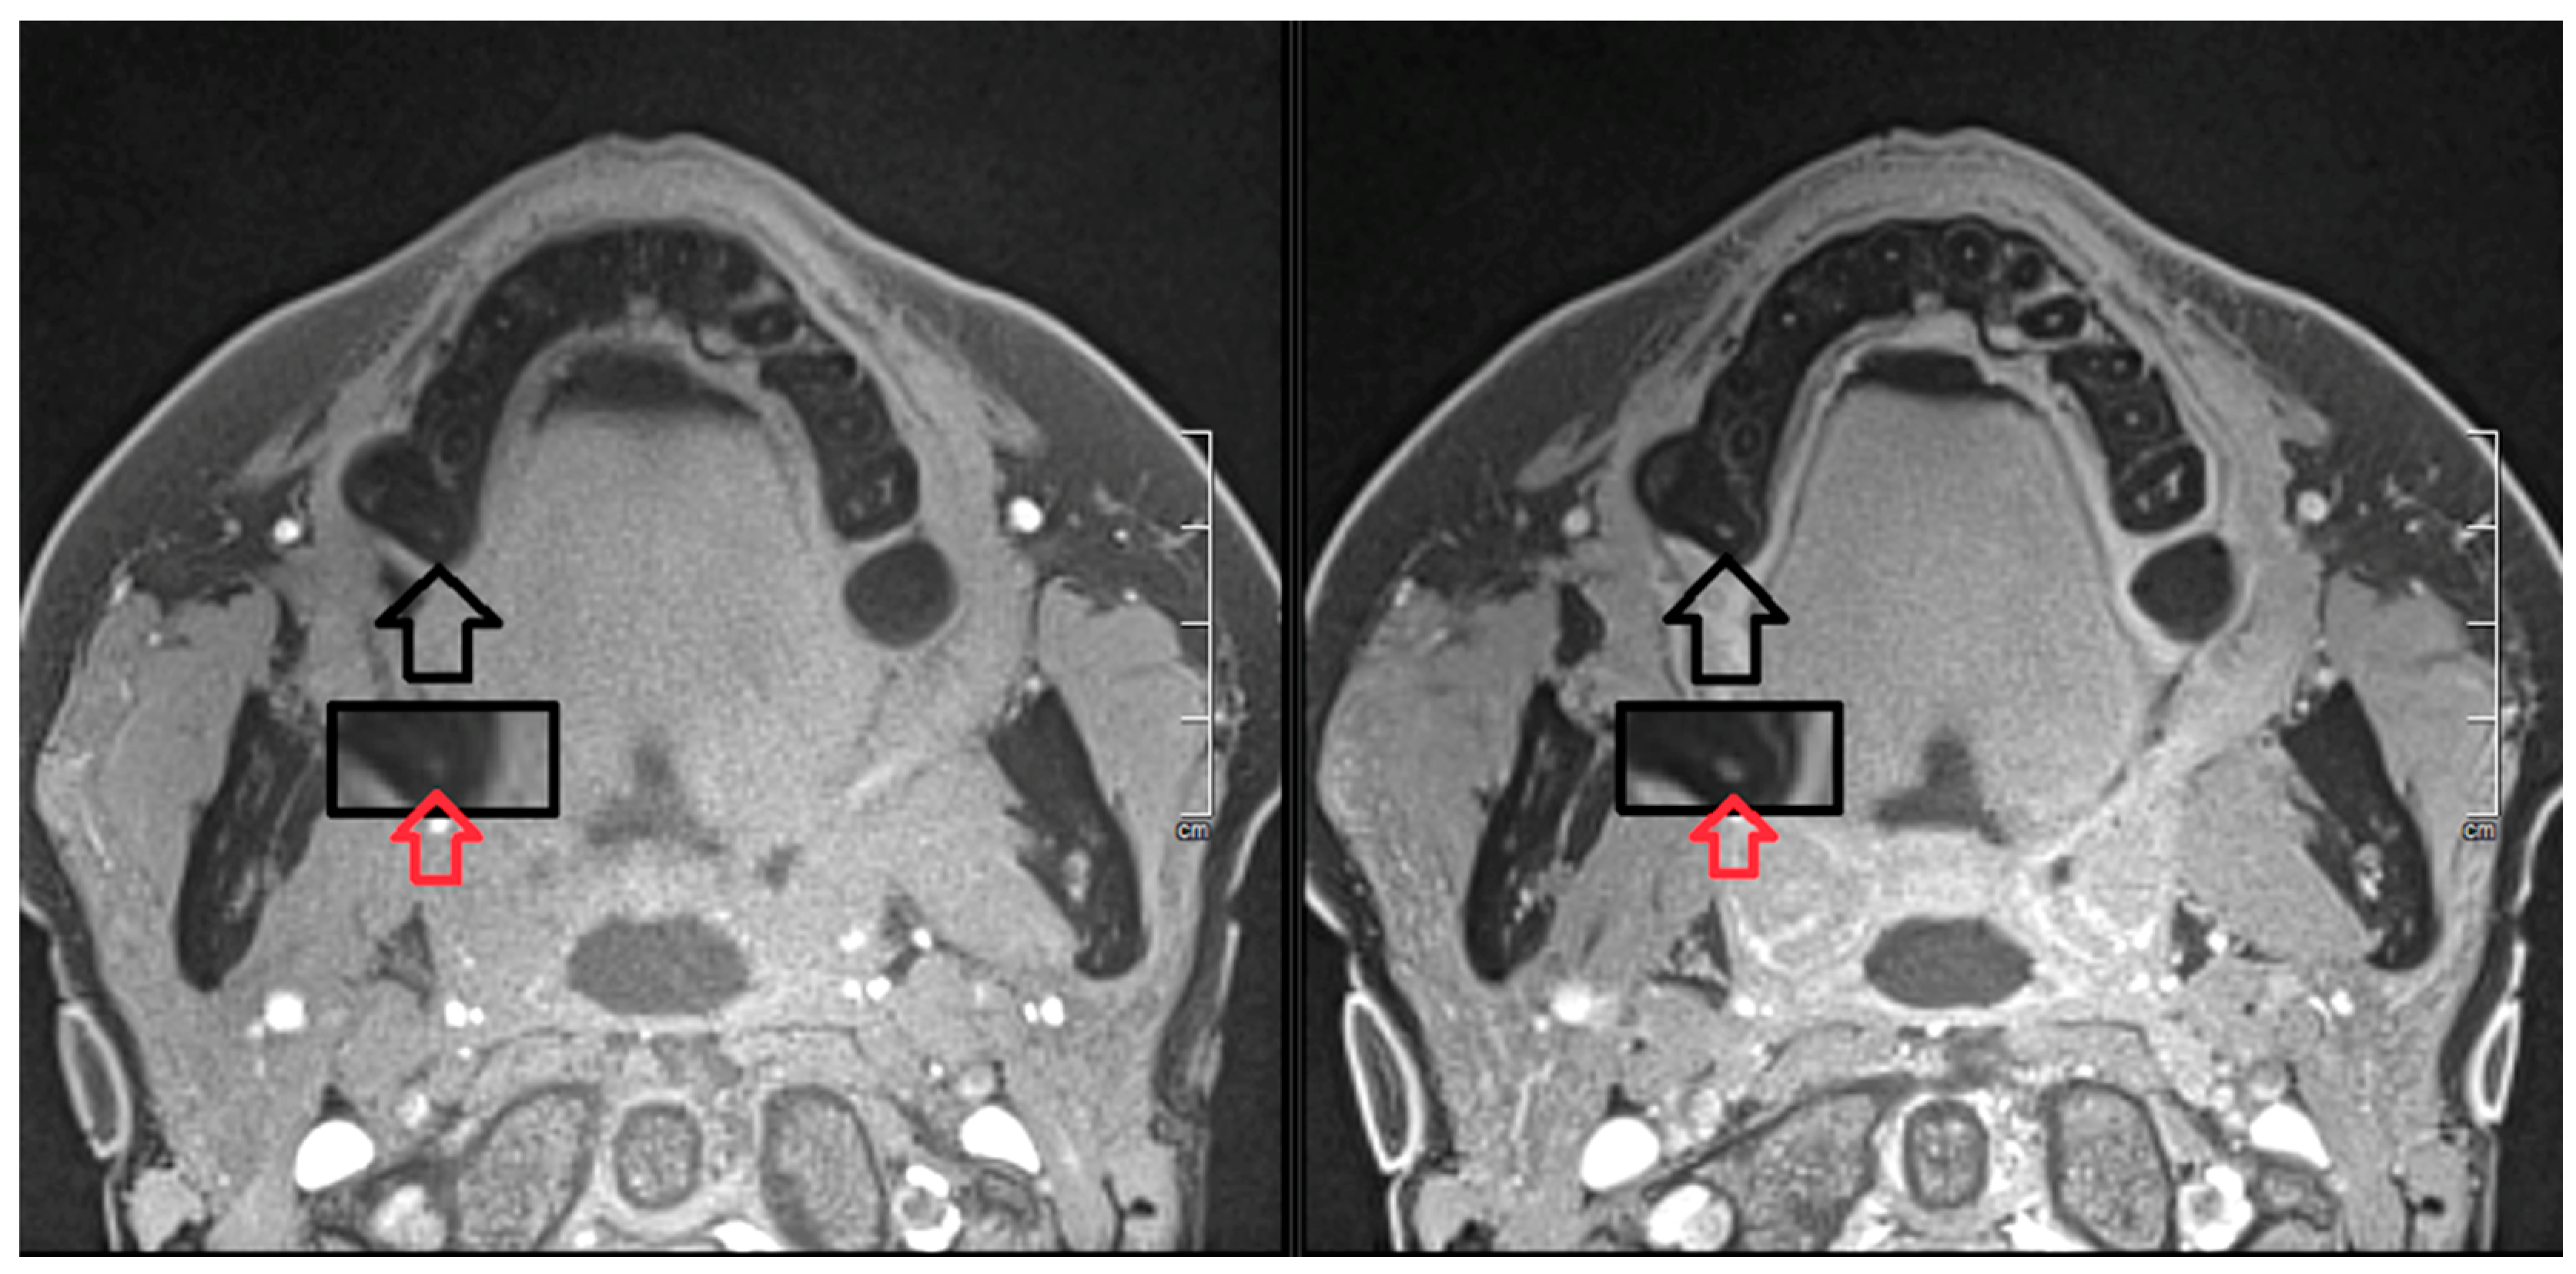

- Assaf, A.T.; Zrnc, T.A.; Remus, C.C.; Khokale, A.; Habermann, C.R.; Schulze, D.; Fiehler, J.; Heiland, M.; Sedlacik, J.; Friedrich, R.E. Early detection of pulp necrosis and dental vitality after traumatic dental injuries in children and adolescents by 3-Tesla magnetic resonance imaging. J. Cranio Maxillofac. Surg. 2015, 43, 1088–1093. [Google Scholar] [CrossRef]

- Kress, B.; Buhl, Y.; Anders, L.; Stippich, C.; Palm, F.; Bähren, W.; Sartor, K. Quantitative analysis of MRI signal intensity as a tool for evaluating tooth pulp vitality. Dentomaxillofac. Radiol. 2004, 33, 241–244. [Google Scholar] [CrossRef] [PubMed]

- Reda, R.; Zanza, A.; Mazzoni, A.; Cicconetti, A.; Testarelli, L.; Di Nardo, D. An Update of the Possible Applications of Magnetic Resonance Imaging (MRI) in Dentistry: A Literature Review. J. Imaging 2021, 7, 75. [Google Scholar] [CrossRef]

- Shah, R.; D’Arco, F.; Soares, B.; Cooper, J.; Brierley, J. Use of gadolinium contrast agents in paediatric population: Donald Rumsfeld meets Hippocrates! Br. J. Radiol. 2019, 92, 20180746. [Google Scholar] [CrossRef] [PubMed]

- Prince, M.R.; Lee, H.G.; Lee, C.H.; Youn, S.W.; Lee, I.H.; Yoon, W.; Yang, W.; Wang, H.; Wang, J.; Shih, T.T.; et al. Safety of gadobutrol in over 23,000 patients: The GARDIAN study, a global multicentre, prospective, non-interventional study. Eur. Radiol. 2017, 27, 286–295. [Google Scholar] [CrossRef]